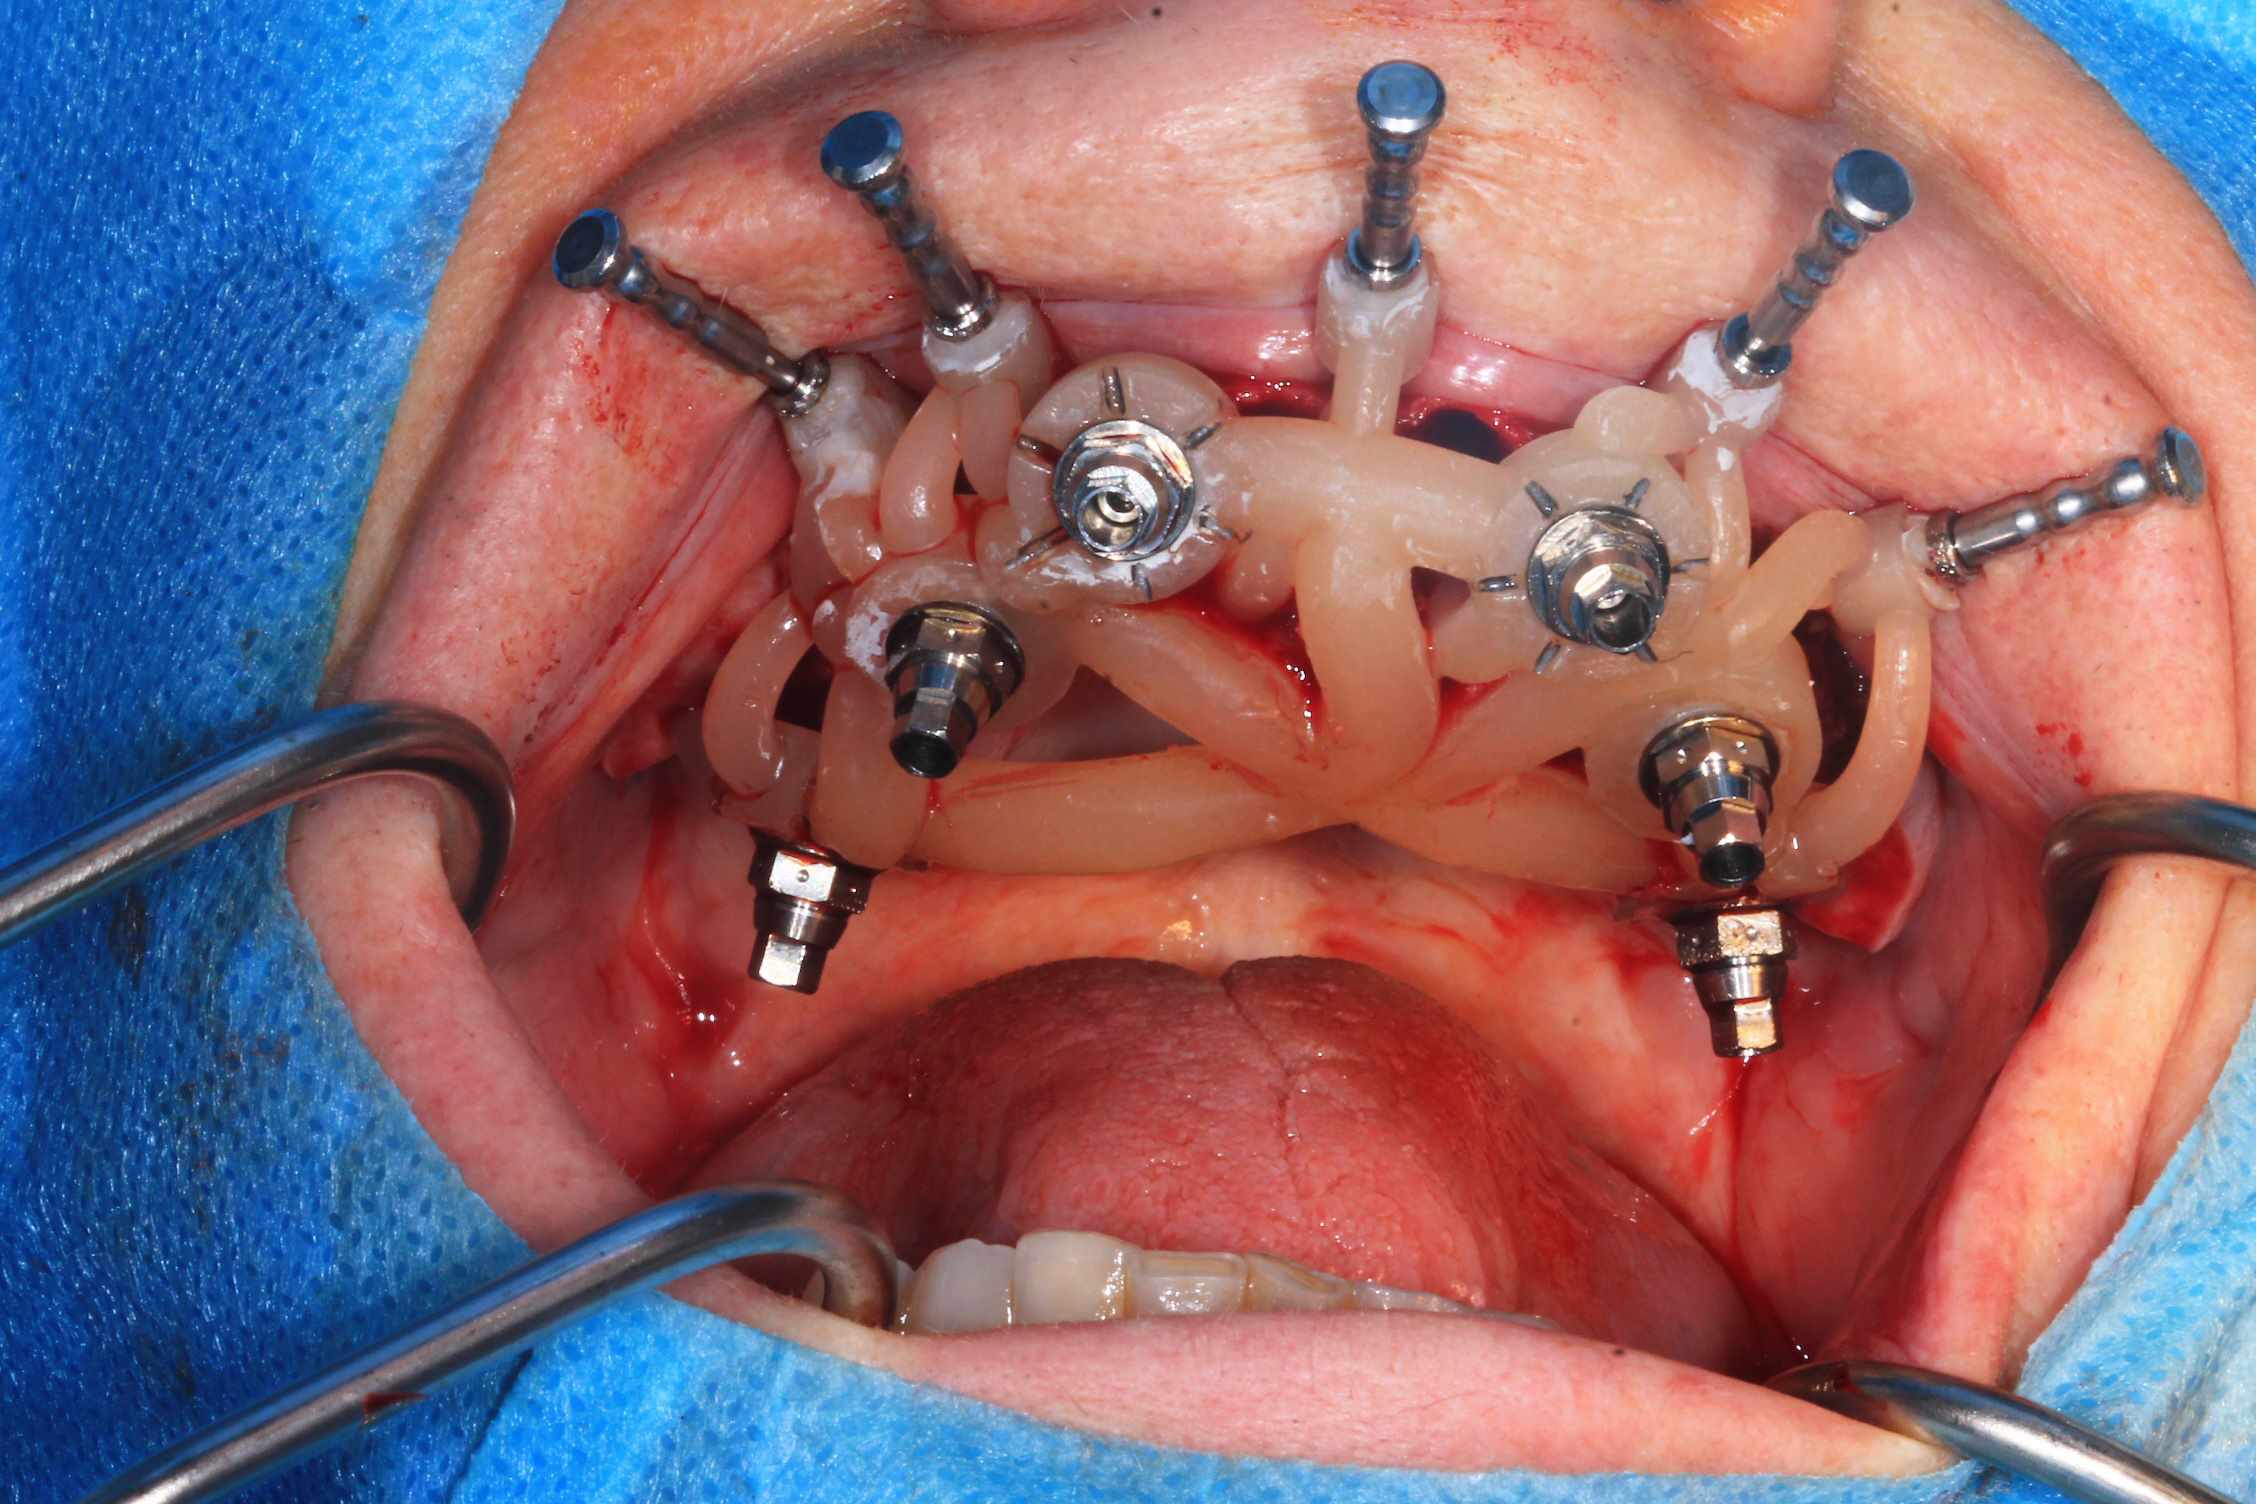

Chrirugie : extraction , mise en place du guide, implants flapless , pose des piliers et du bridge qui tombe pile poil :)

Le but c’est de trouver un point fixe pour stabiliser le guide. Ici Jeff a un guide qui prend appui sur 4 dents sur implants et il a pris le soin d’ajouter 2 clavettes. Plus stable que ça, c’est difficile.

Chir le vendredi matin. au vu de la possibilité de reculer pas mal les implants postérieurs, je trouvais qu'il y avait trop de porté entre les implants : je pars donc sur 6 implants.

Mais malgré les gros renforts, le guide résine n'est pas assez rigide : impossible de poser le bridge en immédiat. obligé de fraiser le bridge ( j'aurais du en prévoir un autre évidé, ce que je prévois pour lundi prochain ) et de mettre des piliers provisoires : 40 m de travail de labo en plus..